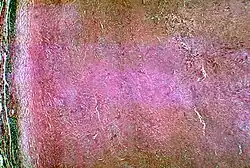

| Histopathological changes in a case of coccidioidomycosis of the lung showing a large fibrocaseous nodule. | |